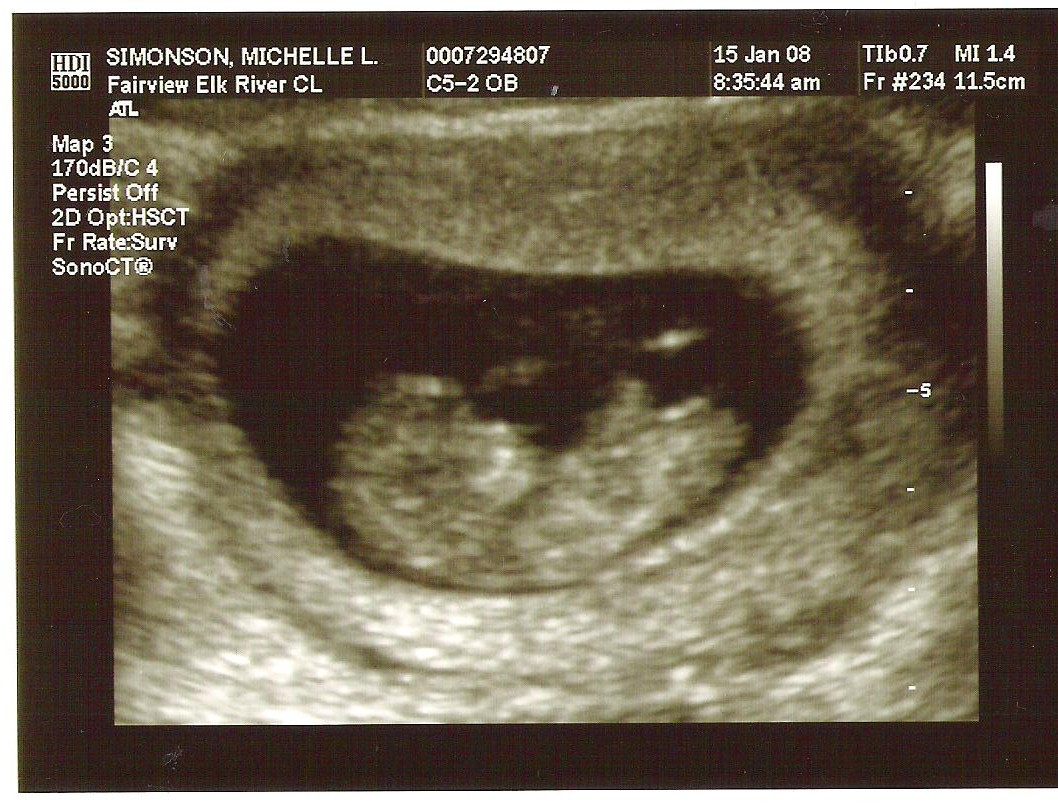

Well Im jumping on the Baby bandwagon too. Just got the first Ultrasound today about 11 weeks along.

Attached Thumbnails